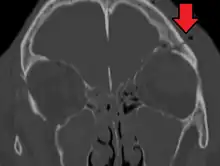

| A subtle temporal bone fracture as seen on CT in a person with a severe head injury | |

They typically require a significant degree of trauma to occur.[1] The break is of at least one of the following bones: temporal bone, occipital bone, sphenoid bone, frontal bone, or ethmoid bone.[1] They are divided into anterior fossa, middle fossa, and posterior fossa fractures.[1] Facial fractures often also occur.[1] Diagnosis is typically by CT scan.[1]

Basilar skull fractures include breaks in the posterior skull base or anterior skull base. The former involve the occipital bone, temporal bone, and portions of the sphenoid bone; the latter, superior portions of the sphenoid and ethmoid bones. The temporal bone fracture is encountered in 75% of all basilar skull fractures and may be longitudinal, transverse or mixed, depending on the course of the fracture line in relation to the longitudinal axis of the pyramid.[6]

The evaluation for basilar skull fracture depends on a CT, as an x-ray is not useful.CT angiography and venography (CTA, CTV) may also be useful as an MRI can be used to ascertain nerve damage[4][8]